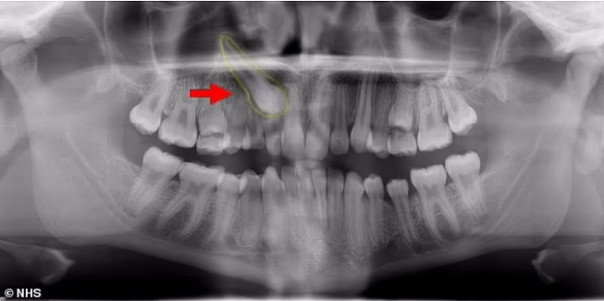

Врачи провели мужчине риноскопию и нашли в одной из ноздрей плотную белую массу, которая не вызывала болевых ощущений. Оказалось, что это эктопический зуб длиной 14 миллиметров, который вырос не там, где ему следовало бы.

Мужчине провели операцию и удалили зуб, вскоре проблемы с дыханием прекратились.